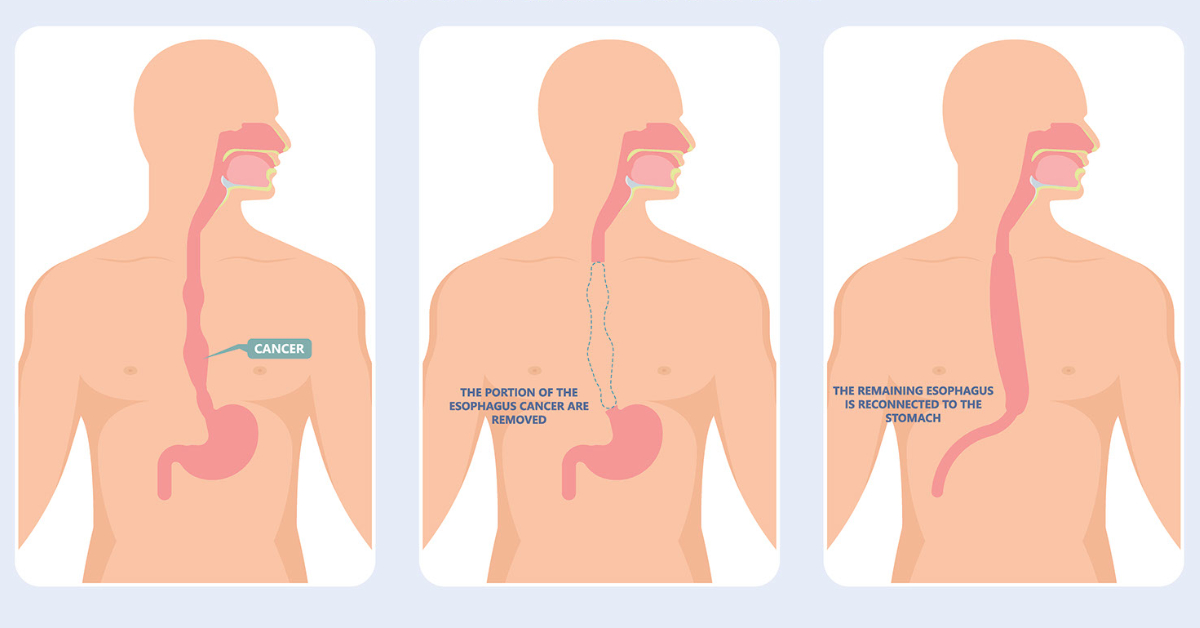

Esophagectomy Purpose Preparation Procedure Aftercare Recovery Risks

Esophagectomy Esophageal Surgery In Mumbai Dr Shitesh Malewadkar